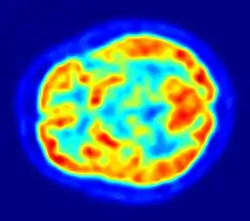

PET imaging with 18F-FDG takes advantage of the fact that the brain is normally a rapid user of glucose. Standard 18F-FDG PET of the brain measures regional glucose use and can be used in neuropathological diagnosis.

- Brain pathologies such as Alzheimer's disease greatly decrease brain metabolism of both glucose and oxygen in tandem. Therefore 18F-FDG PET of the brain may also be used to successfully differentiate Alzheimer's disease from other dementing processes, and also to make early diagnoses of Alzheimer's disease. The advantage of 18F-FDG PET for these uses is its much wider availability. Some radioactive tracers used for Alzheimer's are florbetapir 18F, flutemetamol F18, PiB and florbetaben 18F, which are all used to detect amyloid-beta plaques (a potential biomarker for Alzheimer's) in the brain.

- PET imaging with FDG can also be used for localization of seizure focus: A seizure focus will appear as hypometabolic during an interictal scan. Several radiotracers (i.e. radioligands) have been developed for PET that are ligands for specific neuroreceptor subtypes such as [11C] raclopride, [18F] fallypride and [18F] desmethoxyfallypride for dopamine D2/D3 receptors, [11C] McN 5652 and [11C] DASB for serotonin transporters, [18F] Mefway for serotonin 5HT1A receptors, [18F] Nifene for nicotinic acetylcholine receptors or enzyme substrates (e.g. 6-FDOPA for the AADC enzyme). These agents permit the visualization of neuroreceptor pools in the context of a plurality of neuropsychiatric and neurologic illnesses.

The development of a number of novel probes for noninvasive, in vivo PET imaging of neuroaggregate in human brain has brought amyloid imaging to the doorstep of clinical use. The earliest amyloid imaging probes included 2-(1-{6-[(2-[18F]fluoroethyl)(methyl)amino]-2-naphthyl}ethylidene)malononitrile ([18F]FDDNP)[15] developed at the University of California, Los Angeles and N-methyl-[11C]2-(4'-methylaminophenyl)-6-hydroxybenzothiazole[16] (termed Pittsburgh compound B) developed at the University of Pittsburgh. These amyloid imaging probes permit the visualization of amyloid plaques in the brains of Alzheimer's patients and could assist clinicians in making a positive clinical diagnosis of AD pre-mortem and aid in the development of novel anti-amyloid therapies. [11C]PMP (N-[11C]methylpiperidin-4-yl propionate) is a novel radiopharmaceutical used in PET imaging to determine the activity of the acetylcholinergic neurotransmitter system by acting as a substrate for acetylcholinesterase. Post-mortem examination of AD patients have shown decreased levels of acetylcholinesterase. [11C]PMP is used to map the acetylcholinesterase activity in the brain, which could allow for pre-mortem diagnoses of AD and help to monitor AD treatments.[17] Avid Radiopharmaceuticals has developed and commercialized a compound called florbetapir that uses the longer-lasting radionuclide fluorine-18 to detect amyloid plaques using PET scans.[18]